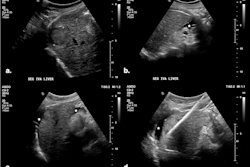

Ultrasound technology developer Exo has launched its latest SweepAI advancements for Exo Iris, which include new capabilities for automatically quantifying inferior vena cava collapsibility and myocardial wall thickness for measuring heart health.

These features will allow for health providers to pinpoint causes of shortness of breath and determine fluid tolerance, the company said.

Exo’s SweepAI assesses the heart’s posterior and interventricular septal wall thickness, providing insights into the impact of chronic hypertension. These tools can help give clinicians confidence when imaging these areas for optimal bedside care, according to the firm.